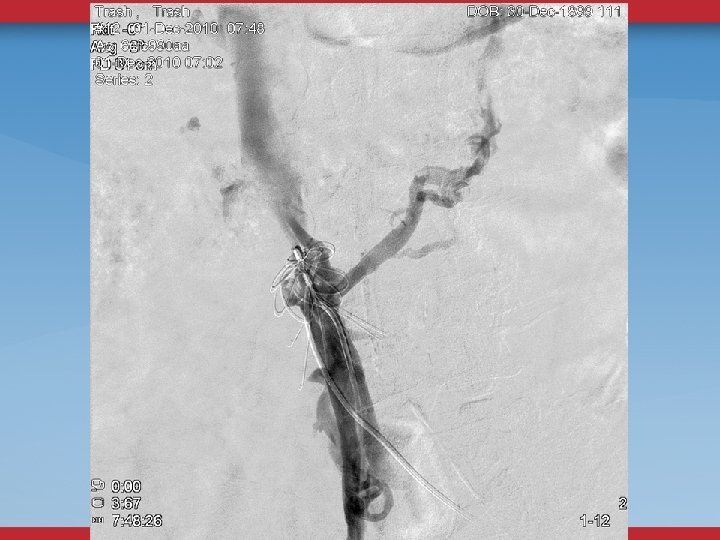

ILIOFEMORAL VENOUS STENTING Chronic non-malignant obstruction 177 limbs stented iliac vein into CFV Focal in-stent stenosis at inguinal ligament 7% (all <50%) In-stent restenosis (>50%) 5% Stent fractures 0 Stent compression 0 Neglen P, Tackett TP, Raju S. J Vasc Surg 2008; 48(5): 1255 -61.

HYBRID PROCEDURES ENDOPHLEBECTOMY OF CFV, FV STENT IVC, ILIAC, CFV Vogel D, Comerota AJ, et al. J Vasc Surg 2012; 55: 129 -135.

DEFINITIVE DIAGNOSTIC/THERAPEUTIC PROCEDURES VENOGRAMS UG sheath placement Femoral, Pop, PTV Flow, Collaterals

VENOGRAMS FEMORAL INFLOW FILLING DEFECTS WILL MISS SOME STENOSES, WEBS

INTRAVASCULAR ULTRASOUND THE ANATOMIC GOLD STANDARD USUALLY BILATERAL IFV/IVC CHOOSE DIAMETER/LENGTH OF BALLOON/STENT POST-STENTING ASSESSMENT